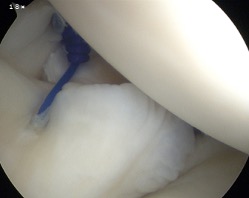

Posterior labral repair

Posterior capsular plication